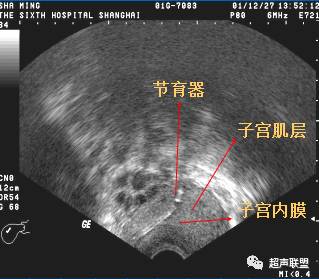

—)、IUD下移(低置)

节育器下移是节育器最常见的位置异常,也是引起避孕失败的最常见原因,节育器下移与子宫的位置、节育器类型、子宫肌瘤等因素有关。前位子宫时IUD下移发生率最高。子宫肌瘤可使子宫位置异常、宫腔变形导致节育器下移。当IUD下移时其脱落的相对危险增加,带器妊娠发生率会明显增高。

IUD上缘与宫底浆膜层之间的距离大于2.0cm,或圆形IUD下缘到子宫内口的距离小于1.0cm,可诊断IUD下移,可在宫内节育器上缘见有子宫内膜回声。IUD进入子宫颈管时,子宫颈管内显示较宽的强回声光条,可伴声影,就此可与子宫颈管回声鉴别。子宫底部患肌瘤,可使正常位置的IUD上缘至子宫底浆膜层的距离增大,应注意与IUD下移鉴别。

宫内节育器下移

声像特点为节育器不在宫腔内而向下移位,节育器下缘达宫颈内口或内口以下,剖宫产切口处常形成憩室,也可是节育器下移到达之处,有时节育器可下移至宫颈管内,或脱出宫颈外口至阴道。

一般节育器的上缘距宫腔底内膜以下一段距离,或上缘距宫底大于2cm即诊断为宫内节育器下移。